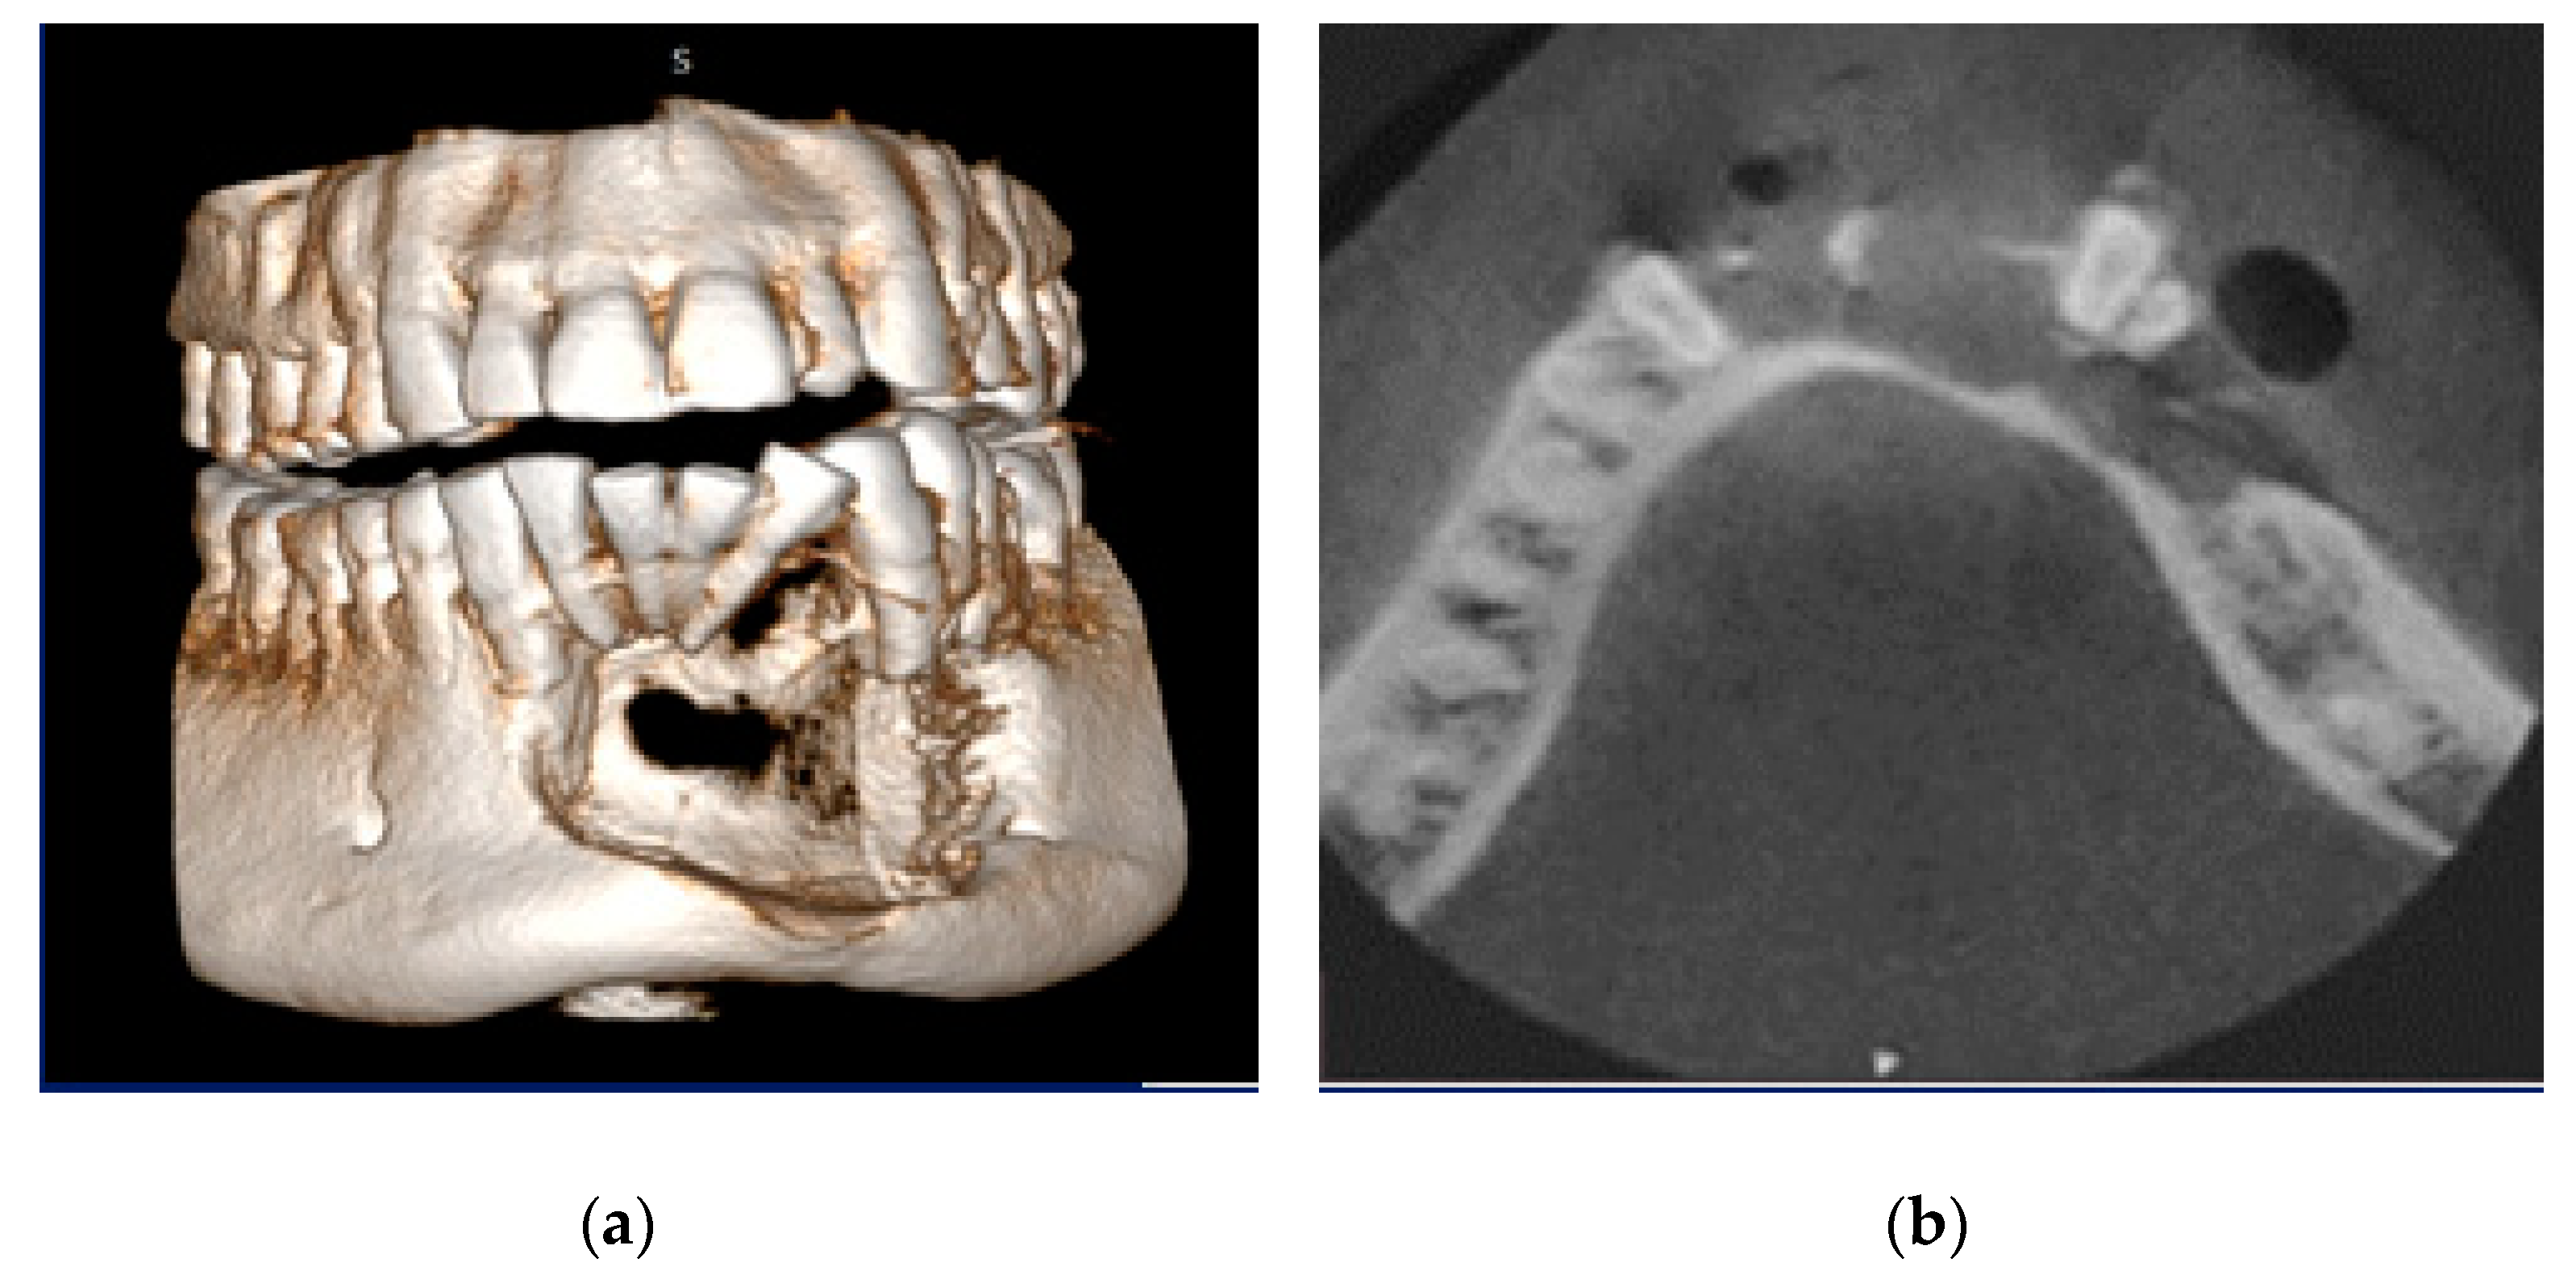

This concept can be explained by a case of swelling in the lower jaw for the past 9 months. No associated pain, numbness, or paresthesia were present. Clinically, distal tipping of 32 and mesial tipping of 33 were evident. Upon vitality testing, 42, 41, 31, and 32 were found to be nonvital. A clinical provisional diagnosis of the radicular cyst was given. The aspiration of the lesion revealed a straw-colored fluid. On CBCT, the pathology in the anterior mandible was evident, with buccal cortical bone destruction, and the internal structure revealed thin septa not extending throughout the lesion (Figure 3a,b). This posed a diagnostic dilemma of either a tumor or a cystic lesion. The gray scale value did not provide insight into the internal structure. The histopathological diagnosis was plexiform ameloblastoma, an odontogenic tumor with centric cystic degeneration.

Figure 3. (a) CBCT images of a clinically diagnosed cystic lesion reveal buccal and lingual cortical bone destruction; (b) Internal structure revealing thin septa that do not extend throughout the lesion. Gray scale value could not differentiate fluid/soft tissue in this case of plexiform ameloblastoma, thus posing a radiological diagnostic dilemma.